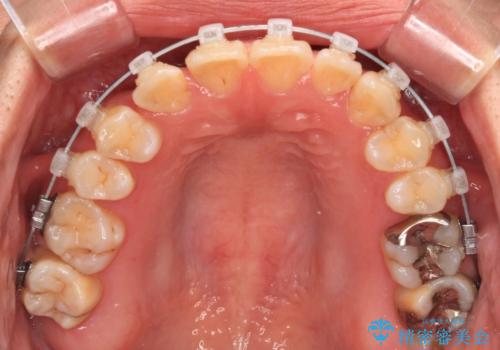

マウスピース矯正が煩わしい ワイヤー装置での非抜歯矯正

- 矯正装置

- メタルブラケット

上下前歯のデコボコを気にして来院された患者様です。

ワイヤー矯正でもマウスピース矯正でも可能でしたが、短期間で、自身の手を煩わせることなく治療を行いたいとのことで、ワイヤー装置にて矯正治療を行うこととしました。

舌の突出癖により、治療過程でスペースが多くできましたが、舌のトレーニングを頑張っていただき、1年強で終えることができました。